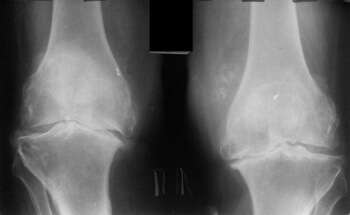

Endoprótesis de rodilla, foto

El efecto de la artrosis en el cartílago de la articulación de la rodilla.